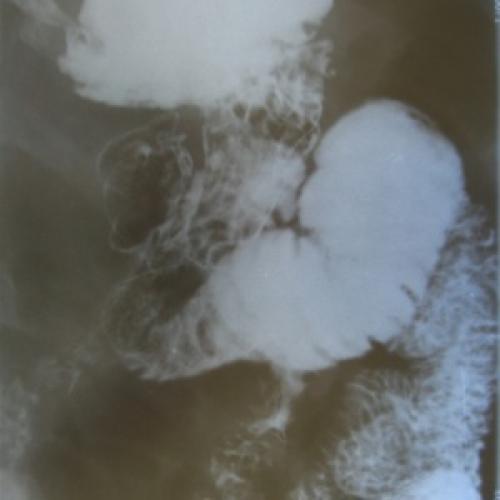

В настоящей статье представлены результаты оперативного лечения 114 пациентов, страдающих гастродуоденальными язвами, осложненными суб- и декомпенсированным…

Roux-реконструкция как метод хирургической коррекции постгастрорезекционных…

В работе обоснована целесообразность использования Roux-реконструкции верхних отделов желудочно-кишечного тракта при лечении постгастрорезекционных и постгастрэктомических…

Профилактика регургитационных осложнений при дистальной резекции пищевода

В работе представлен анализ результатов клинического применения эзофагогастропластики с формированием антирефлюксного пищеводно-желудочного анастомоза…